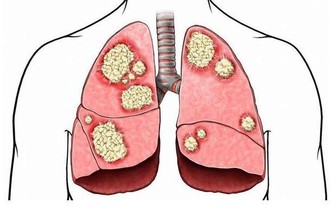

事實上,已有多項研究表明,長期睡眠不足,患結直腸癌、甲狀腺癌、肺癌等癌症的風險都會增加。

相比睡眠時間在7~7.5個小時的男性,睡眠不足(≤6.5小時)的男性,發生肺癌的風險增加112%。